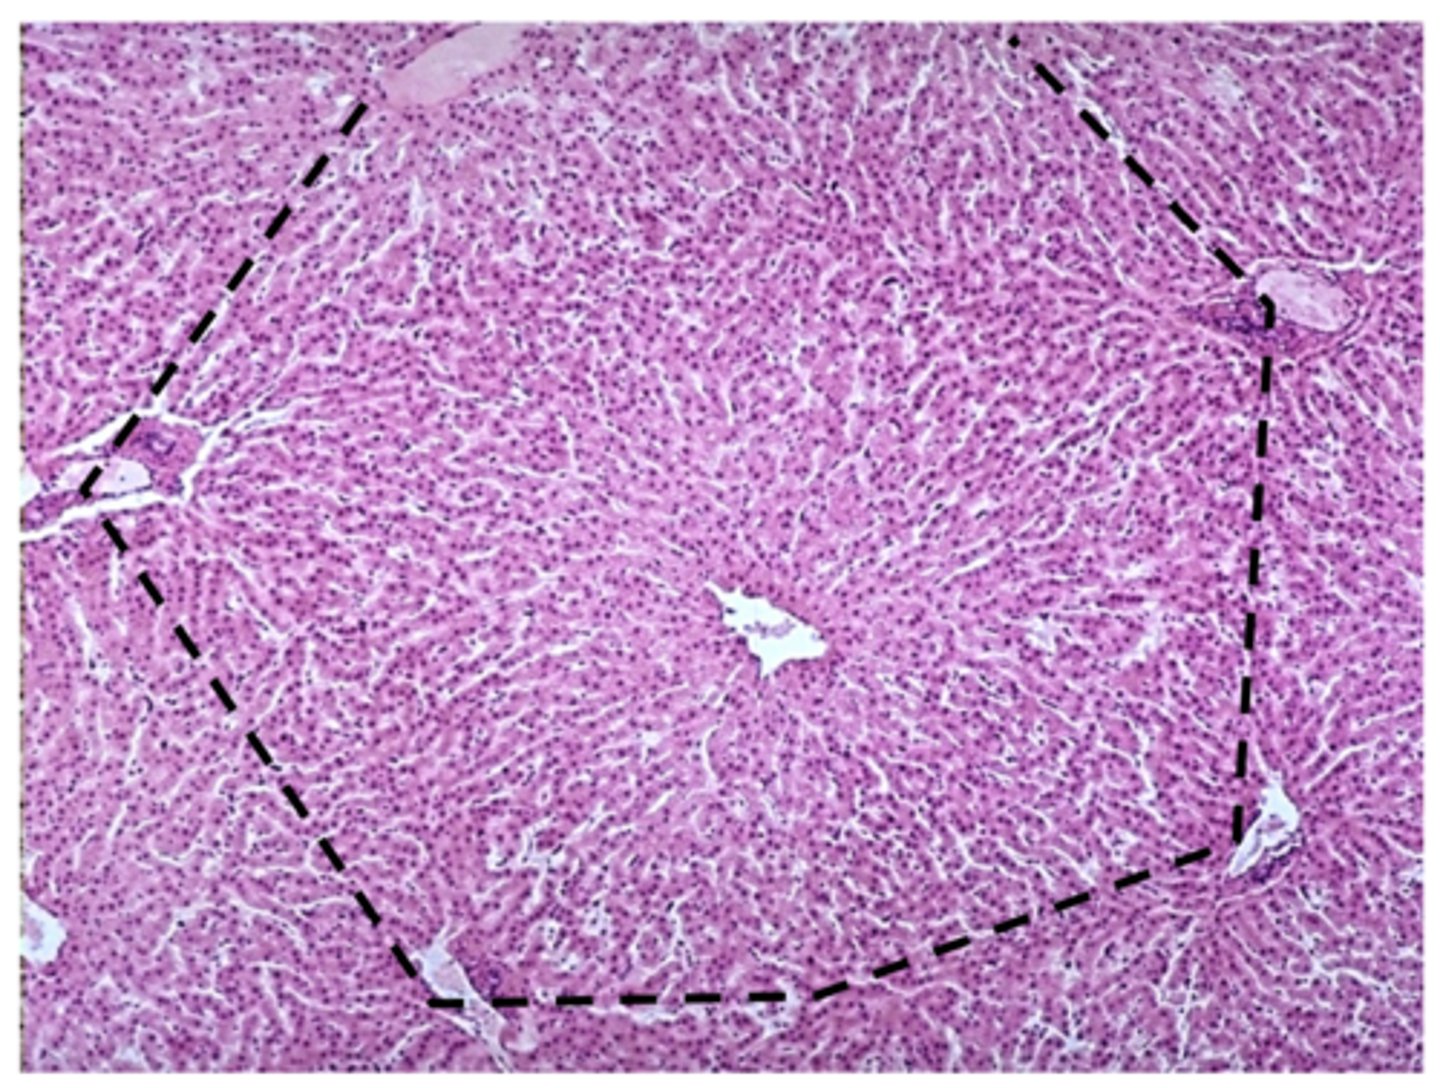

what organ is this?

liver lobule

what is this?

hepatocytes

central vein

name this structure

sinusoids

name this structure in the liver

portal area

name structure B